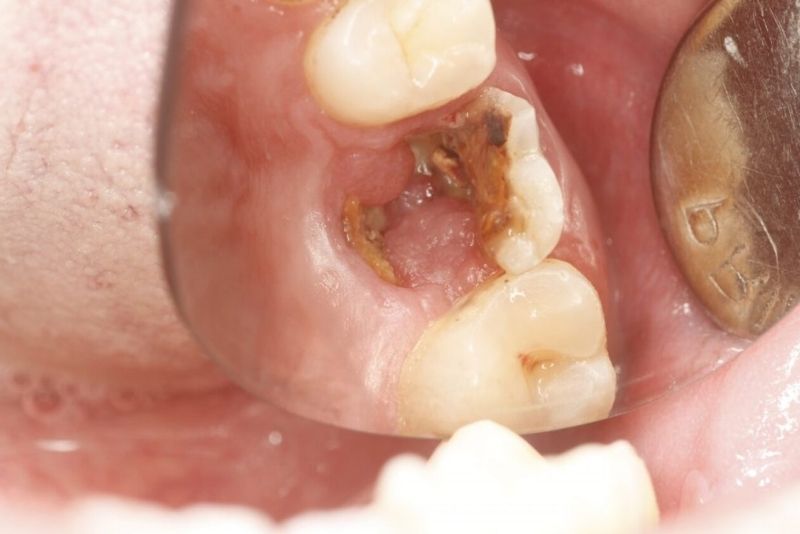

Tình trạng răng vỡ lớn nên bọc sứ

3. Khi nào răng lấy tủy chưa cần bọc sứ ngay?

Răng đã lấy tủy chưa cần bọc sứ ngay trong một số trường hợp như: răng còn nhiều mô răng lành, cấu trúc thân răng vững chắc, vị trí răng ít chịu lực nhai (thường là răng cửa), và đã được trám kín tốt sau điều trị tủy. Khi đó, miếng trám có thể tạm thời bảo vệ răng và duy trì chức năng ăn nhai.

Tuy nhiên, do răng mất tủy sẽ giòn và dễ nứt vỡ theo thời gian, bác sĩ vẫn thường khuyến nghị bọc sứ ở giai đoạn phù hợp để bảo vệ răng lâu dài.